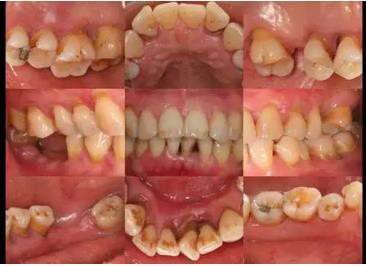

通常,第一步是拍照,牙周科標(biāo)準(zhǔn)口內(nèi)照片主要為了顯示軟組織情況。全口分為9個(gè)區(qū),頰舌側(cè)都需要清晰的暴露。拍照的過程要快而準(zhǔn)。我們也是在大量重復(fù)的實(shí)戰(zhàn)演練中練就而成,下面一組照片基本上一分鐘之內(nèi)可以完成。